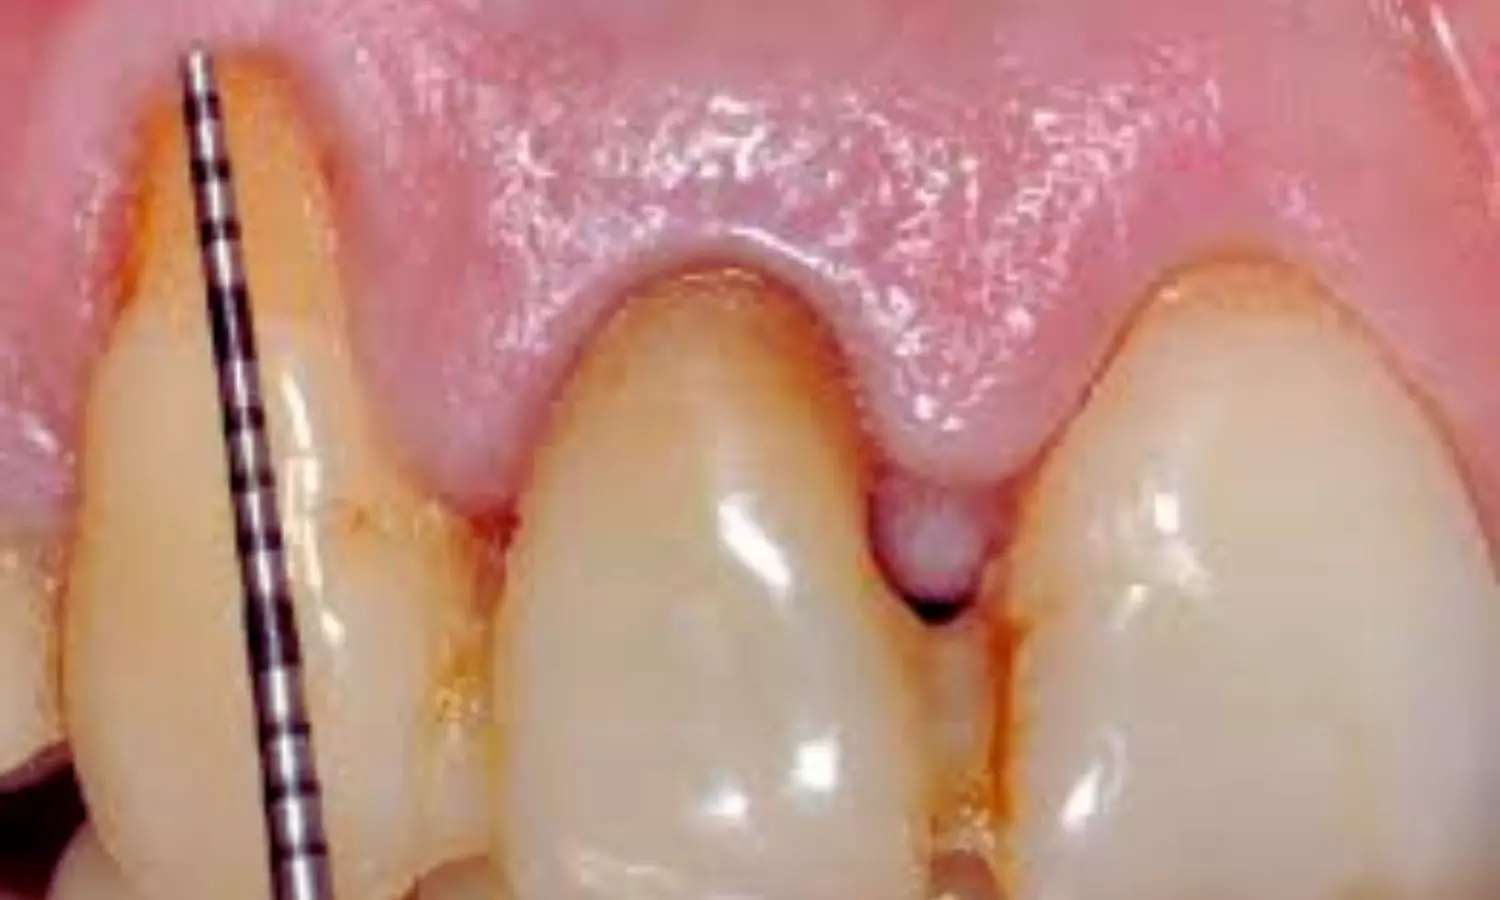

Gingival recession, where the gum margin moves apically and exposes the root surface, is frequently seen in clinical practice. Importantly, nearly half of these cases are associated with NCCLs—tooth structure losses near the gum line that are not caused by decay. When both conditions coexist on the same tooth, they are referred to as combined defects (CDs). These situations are more complex than isolated gingival recession on an intact tooth and often require tailored treatment strategies.

- When more advanced defects are present, particularly B+ or V-shaped non-carious cervical lesions, a combined treatment approach becomes necessary.

- In such advanced cases, restoring the cervical lesion with composite materials along with a root coverage procedure provides improved functional and aesthetic outcomes.

- Approximately 25% of combined defects fall into this more complex category, highlighting the importance of thorough clinical assessment and careful treatment planning.